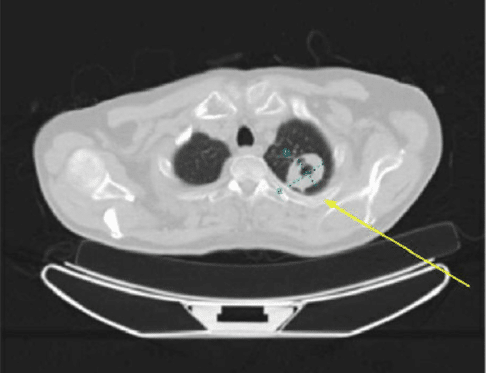

Mycobacterium Avium Complex Infection Presentation with Rare Fungal Hyphae Diagnosed After Routine Preventive Screening

Background: This case report highlights a rare but serious presentation of mycobacterium avium complex (MAC) in conjunction with a rare...Read More